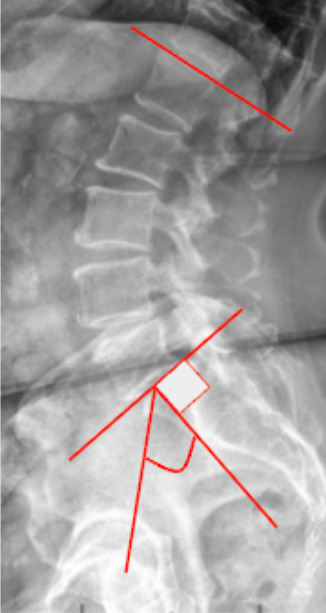

PI-LL Mismatch

The Pelvic Incidence–Lumbar Lordosis (PI–LL) Mismatch quantifies the relationship between pelvic morphology and lumbar curvature, serving as a key indicator of sagittal balance and spinal harmony.

This parameter compares a fixed anatomical measure (Pelvic Incidence) with a functional curvature (Lumbar Lordosis). Ideally, lumbar lordosis should closely match pelvic incidence to maintain an energy-efficient upright posture and minimize compensatory mechanisms.

A mismatch (PI–LL > 10°) suggests sagittal malalignment, leading to compensatory pelvic retroversion, knee flexion, and increased muscular fatigue. This metric is critical in preoperative planning and postoperative alignment assessment, especially in adult spinal deformity correction.

• Measure Pelvic Incidence (PI):

• Identify the center of the femoral heads (use midpoint if both are visible).

• Identify the center of the superior endplate of S1.

• Draw a line connecting these two points (femoral head center → sacral endplate center).

• Draw a line perpendicular to the S1 endplate.

• The angle between the connecting line and the perpendicular is the Pelvic Incidence (PI).

• Measure Lumbar Lordosis (LL):

• Identify the superior endplate of L1 and superior endplate of S1.

• Draw lines along both endplates.

• Measure the angle between these two lines—this is the Lumbar Lordosis (LL).

• Calculate PI–LL Mismatch:

PI-LL Mismatch = Pelvic Incidence - Lumbar Lordosis

• Record the result in degrees (°). A positive mismatch (>10°) indicates inadequate lordosis relative to pelvic morphology.